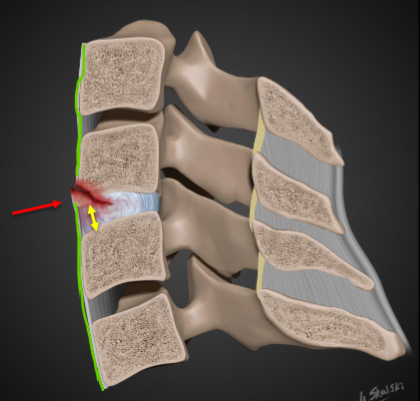

What is a flexion teardrop fracture?

Highly unstable.

• The posterior and anterior longitudinal

ligaments are disrupted.

• Posterior displacement of the vertebra the

spinal canal.

• Disruption of the posterior portion of the

vertebra above.

• Stress applied to the anterior longitudinal

ligament causes it to avulse from the

vertebral body along with a “teardrop”

shaped bony fragment.

• Most common at C5/6 and C6/7

What is an extension tear drop fracture?

Due to forced extension of the

neck with a resultant avulsion of

the antero-inferior corner of a

vertebral body by the anterior

longitudinal ligament.

• Stable in flexion but unstable in

extension.

• Not considered as serious as a

flexion tear drop fracture.

• Anterior disc space widening.

• Can result in cord damage